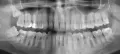

Третий день болит зуб, усиливается боль по ночам и в положении лежа. При накусывании боли нет. При пальпации десен боли нет. Реакция на холодное ― боль усиливается, потом стихает. При этом холодный компресс на щеку со стороны больного зуба боль снижает.

Боль в районе 7 и 8 зуба на нижней челюсти. 7-ка пролечена 6 лет назад, поставлена кальциевая прокладка, зуб не депульпирован. 8-ка имеет кариес. Боль также при пальпации под челюстью чувствуется. При этом боль не острая, а ноющая, тянущая, распирающая. Не стреляет.

Вчера была у стоматолога. Предположение ― пульпит 8-ки, нужно удаление. Это первый коренной зуб, который предстоит удалить. Большой страх перед этой процедурой. Читала много, боюсь, чтобы не повредили лишнего. Корни 8-ки загнуты. Боюсь, чтоб они не лежали в нервном канале, и при удалении не было проблем.

Хочу сразу успокоить ― корни у нижней восьмерки в канале лежат очень редко, за 25 лет я такого не видел и даже не слышал. А вот корни верхних зубов бывает располагаются в гайморовой пазухе, вот это действительно сложное удаление. Нижние же зубы мудрости сложны в удалении только, если они лежат под костью, полностью заросли, так называемые ретинированные зубы.

Но у Вас, если его смотрел доктор и предположил пульпит, очевидно, что коронковая часть зуба видна. Даже, если корни загнуты, для хирурга-стоматолога ― это ординарная ситуация. Удаление, возможно, будет считаться сложным, но это означает лишь то, что врачу придется приложить чуть больше усилий.